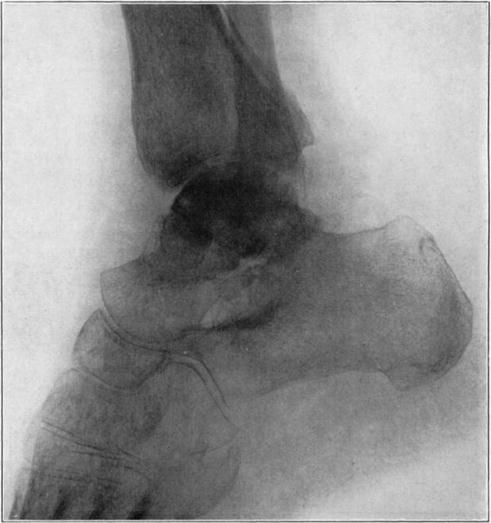

Necrosis of Os Calcis

In fracture of the neck of the os calcis the body may rarely have so much of its blood supply cut off that it undergoes extensive necrosis. Its subsequent history is analagous to that of a necrotic proximal fragment in intracapsular fracture of the neck of the femur. If bony union between the fragments follows, the necrotic body will be invaded gradually by blood vessels, fibrous, osteogenic, and myelogenous tissue, and a gradual replacement of the necrotic by living elements will be brought about. The replacement may be incomplete and the necrotic portion located farthest from the fracture may be broken down by weight-bearing before the ingrowing tissue reaches it, thereby leading to deformity and permanent derangement of the bone.

The following cases are illustrative of this condition.

Case 2. Seventy-four days after fracture of neck of astragalus, posterior dislocation of body, and reduction by operation. Body necrotic and retained normal density. Atrophy of disuse of other bones. Bony union of fracture.

Case 2. One hundred and sixty days after fracture. Body slightly reduced in density near fracture due to invasion from neck.

Case 3. Fresh fracture of neck of astragalus and chip off superior and posterior portion of os calcis.

Case 3. Two hundred and seventy-four days after injury. Fracture of astragalus united. Superior and posterior part of body broken down and irregular while remaining portion dense and transformed. Indicative of necrosis of body with secondary changes.

Case 3. Eighteen months after injury, showing a defective but gradually reforming articular portion of the body of the astragalus.

The blood supply of the astragalus is derived mainly from a branch of the arteria dorsalis pedis which traverses the sinus tarsi lateral to the neck and breaks up to enter the bone near the junction of the neck and body along the lateral and inferior surfaces. There are very small branches entering the bone mesially and posteriorly at points of ligamentous and capsular attachments. Apparently when there is a fracture along the junction of body and neck the important vessels to the body are interrupted and there may be insufficient circulation through the remaining vessels, so that aseptic necrosis of a large part or all of the fragment follows. It is evident from the partial collapse which occurred in Case 3 that when necrosis of the body is diagnosed, the limb should be protected from weight-bearing for at least several months,—until union, revascularization, and transformation of necrotic area has been largely brought about. It seems probable that some of the bad results that have been reported in fracture of the neck of the astragalus, either united or ununited, have been due to overlooked aseptic necrosis of the body.